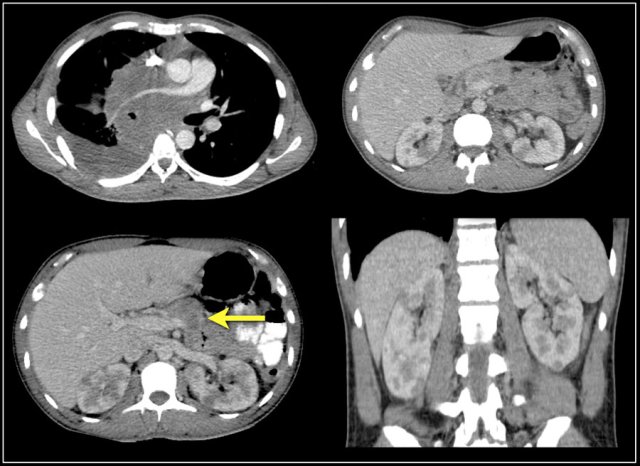

Bean-type lesions

The radiologic features of bean-type lesions are generally nonspecific.

Notice the similar appearance of the lesions in the figure.

The differential diagnosis can often be suggested by integrating clinical and imaging data.

- A central infiltrating lesion that fills the renal pelvis in an older patient is most likely a transitional cell carcinoma (TCC), also called urothelial cell carcinoma (UCC).

- An infiltrative mass in a young patient with sickle cell trait is likely to be renal medullary carcinoma.

- Multifocal and bilateral lesions or diffuse renal infiltration in combination with lymphadenopathy and involvement of other organs is suggestive of lymphoma.

- Multifocal and bilateral renal lesions in known malignancy is suggestive of metastases, although in case of a single infiltrative mass, infiltrative renal cell carcinoma must be considered.

- In patients with pain and signs of infection, the diagnosis is pyelonephritis.

- Wedge-shaped lesions are suggestive of infarction.